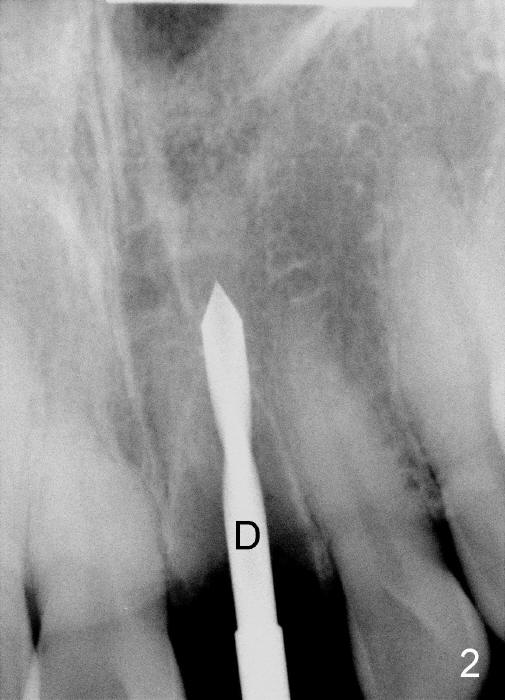

The upper right central incisor (Fig.1: #9) fractures subgingivally due to trauma for a 40-year-old man.  The incisive canal is large (I) and close to the root of the central incisor.  After extraction, the osteotomy (Fig.3b, 4: O) is made with 2 mm pilot drill (Fig.2: D) on the lingual wall (Fig.3a: L) of the socket (Fig.3a: S).  To push the incisive canal mesially, the osteotomy is enlarged by 3.5x21 mm and 4x21 mm tapered osteotomes (Fig.5,6: O).  Due to the lingual slope (Fig.7a arrow), the osteotome (blue outline) starts to deviate bucally.  To reduce this tendency, the coronal portion of the lingual slope is removed (Fig.7b: yellow circle).  The final implant (4.5x20 mm) is able to be placed as lingually as possible (Fig.7c, 8).